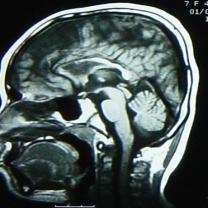

核磁檢查:右側(cè)大腦半球皮層大部分呈長T1、長T2信號,其中右額部為與腦脊液信號相同的囊性病變,與右側(cè)腦室相溝通,右側(cè)腦室擴(kuò)大,左側(cè)腦室大小正常,中線結(jié)構(gòu)居中。MRI診斷:右側(cè)額顳頂枕葉腦軟化,右側(cè)腦室穿通畸形(圖2)。

圖2 MRI顯示右側(cè)大腦半球大部分呈長T1、長T2信號,右額部為與腦脊液信號相同的囊性病變,與右側(cè)腦室相溝通,右側(cè)腦室擴(kuò)大,左側(cè)腦室大小正常,中線結(jié)構(gòu)居中。